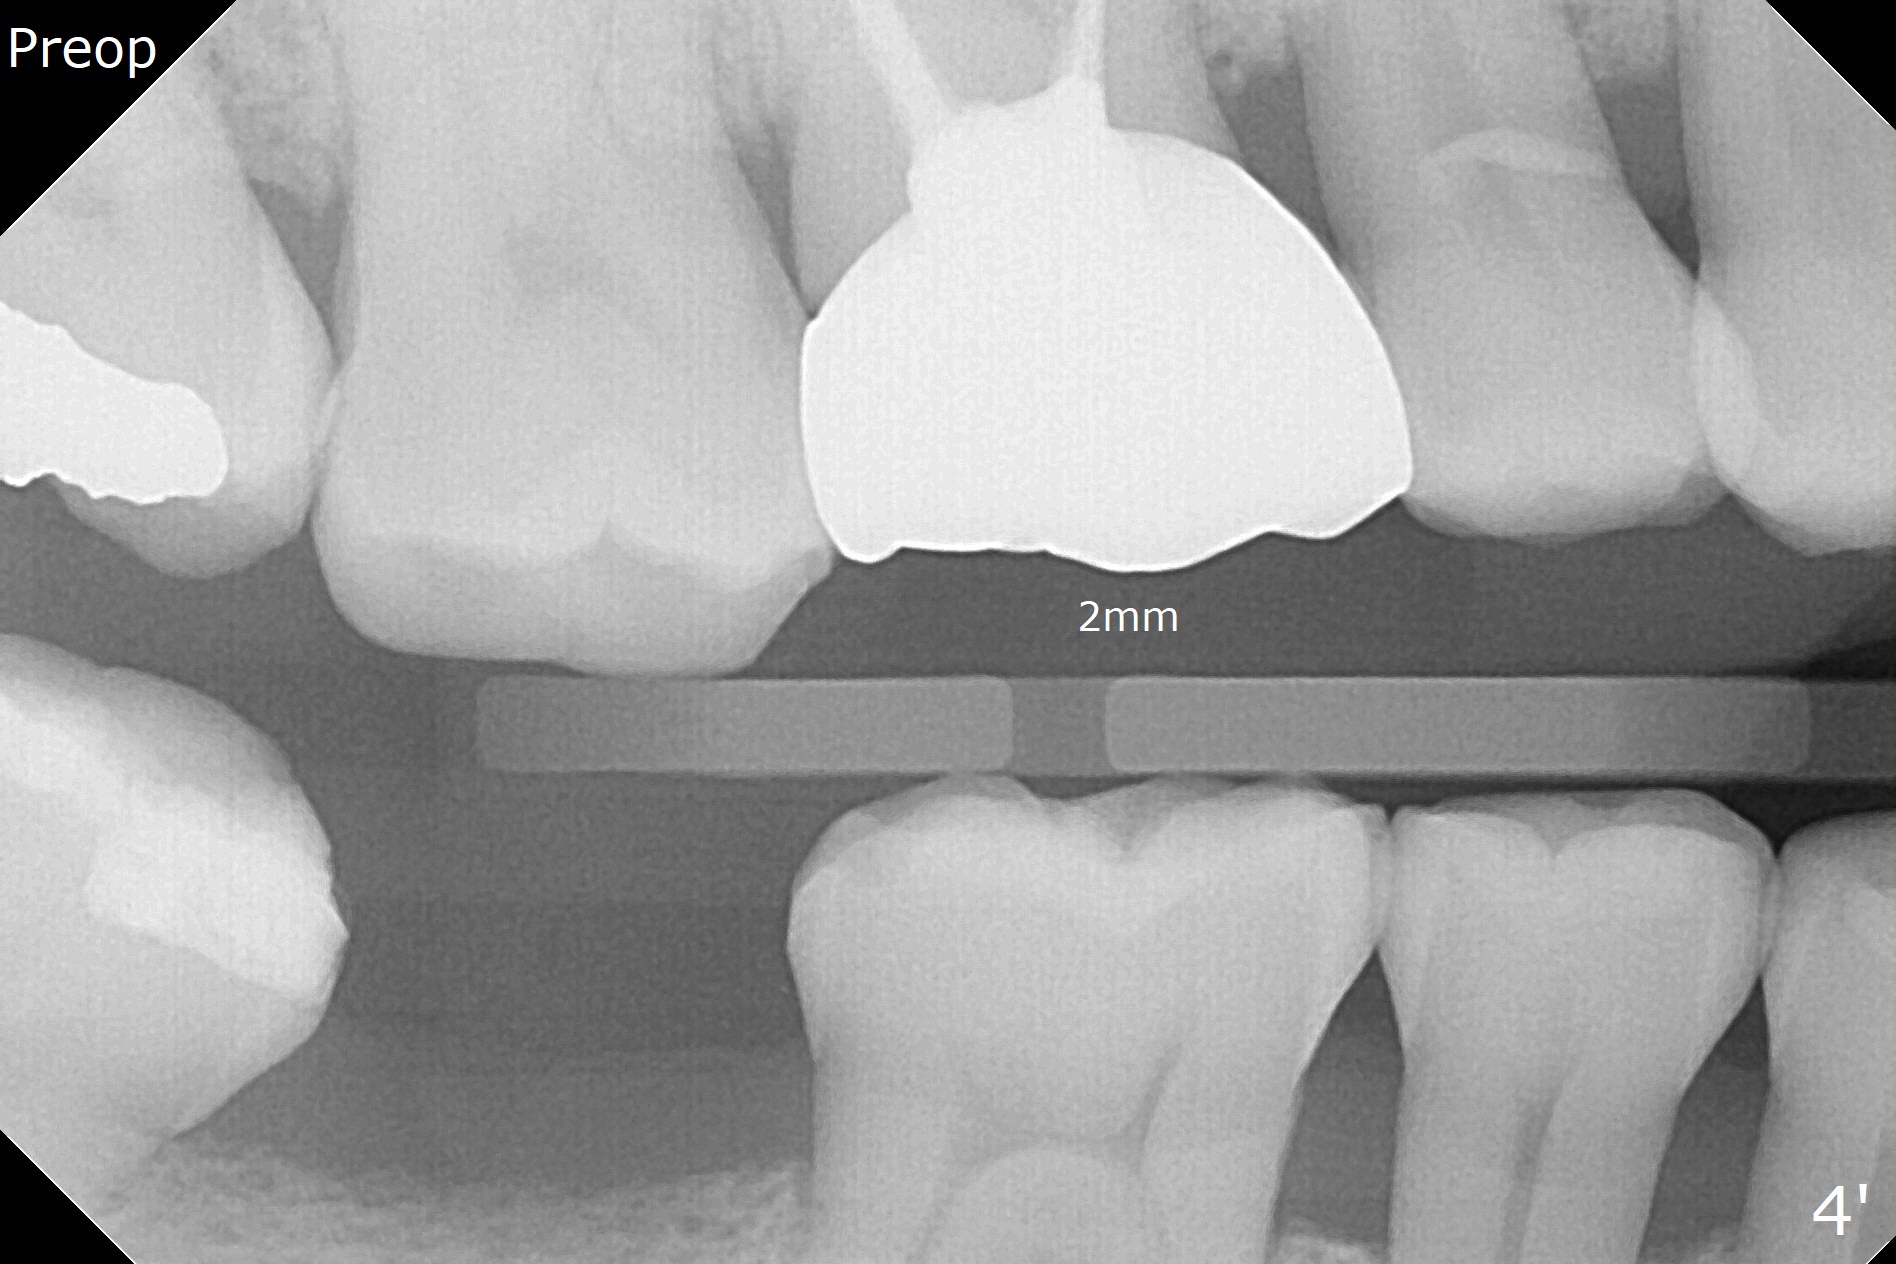

In fact 5x10 mm implant placement with guide requires using 5 mm cortical tap (Fig.1). When a 6x4 mm healing abutment is placed slightly supragingival, the clearance with the opposing supraerupted tooth is ~ 2 mm. It suggests that orthodontic intrusion is required for restoration. In fact the patient is incompliant with orthodontic mini-implant placement and retraction. When the implant at #31 is osteointegrated 4.5 months postop (Fig.2), it is used an anchor with an abutment and a provisional to intrude the opposing tooth. The final crown is cemented 10 months postop (Fig.3) with occlusal clearance (Fig.3' *). The contacts between #2 and 3 and between #31 and 32 are loose with papillary inflammation 5 months post cementation. It is planned to remove #31 crown/abutment for pick up impression/porcelain addition. Instead the crown is removed. After removing #32 MO composite with minor 2nd caries, new composite is placed (Fig.4 *) while the crown is reseated. When the crown is recemented, bitewing shows open margin (Fig.4), but the contact is wide and tight. After occlusal adjustment, occlusal contact at #31 and 32 mesial is heavier than that at #30. #3 crown is recommended. The occlusal table difference betweeen the upper 1st and 2nd molar is ~ 2 mmm preop (Fig.4'), whereas the difference is ~ .6 mm postop (in combination of occlusal equilibrium and intrusion of the upper 2nd molar (Fig.4)). It seems that orthodontic intrusion is not efficient in a male with bruxism. There is mild lingual (L) and distal bone loss 1.5 years post cementation (Fig.5) when CT is taken for #3 immediate implant. Lower Molar Immediate Implant, Armaments Xin Wei, DDS, PhD, MS 1st edition 07/12/2018, last revision 11/28/2020